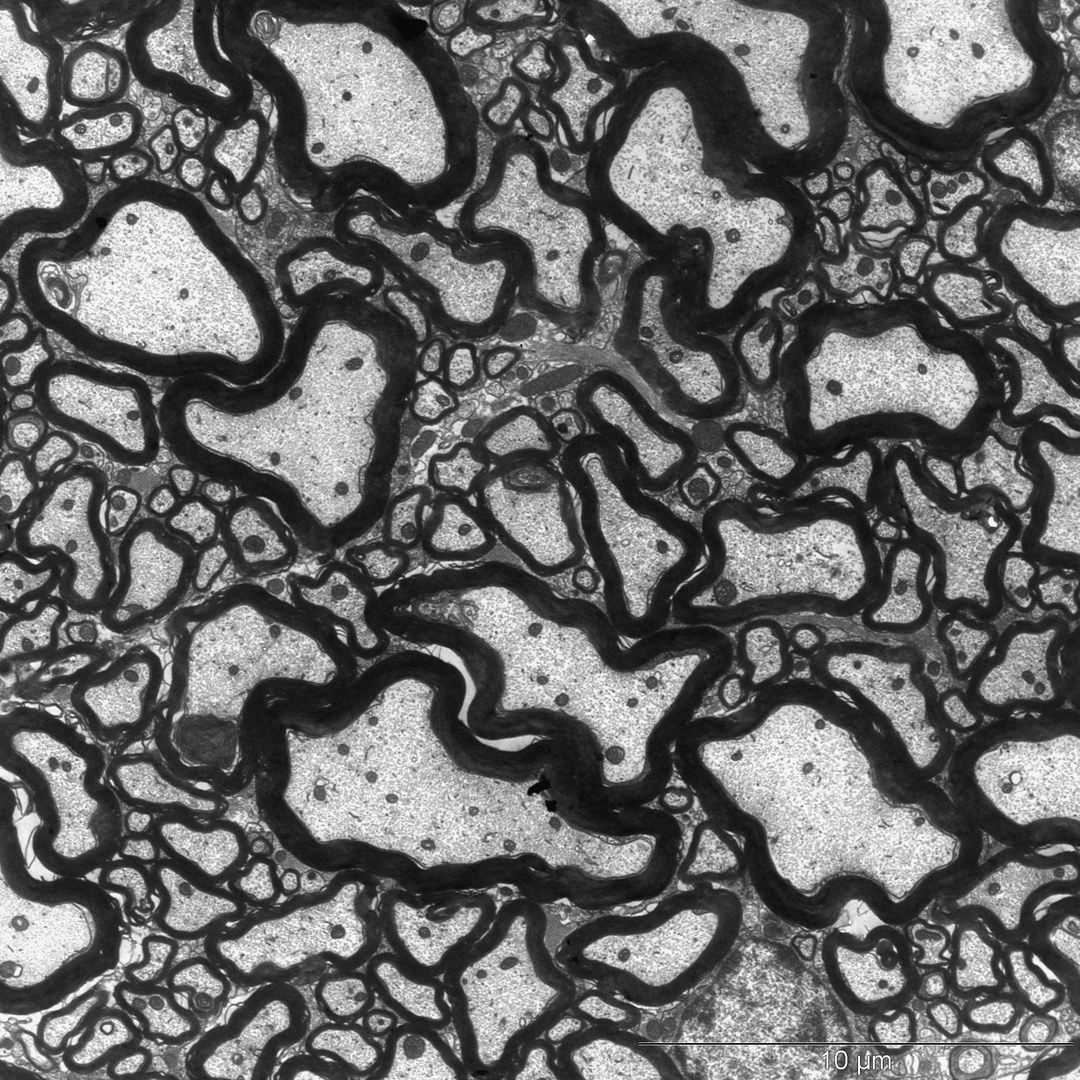

研究人员确实找到了他们要找的东西。当他们将牛奶中的成分酪蛋白和一种效果增强剂一起给动物服用时,小鼠就会出现神经系统紊乱。电子显微镜显示,神经纤维周围的绝缘层--髓鞘受到了损害。这种类似于脂肪的物质可以防止短路,另外还可以大大加速刺激的传导。

在多发性硬化症中,身体的免疫系统破坏了髓鞘。其后果从麻痹和视力问题到运动障碍不等。在极端情况下,患者需要坐轮椅。绝缘鞘在小鼠体内也被大量穿孔--显然是由酪蛋白的施用引发的。“我们怀疑原因是一种错误的免疫反应,类似于多发性硬化症患者的情况,”Rittika Chunder解释说,她是Kürten教授研究小组的一名博士后研究员。“身体的防御系统实际上是在攻击酪蛋白,但在这个过程中,它们也破坏了参与髓鞘形成的蛋白质。”